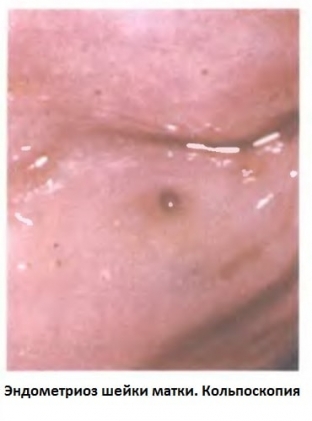

Важливу роль діагностичному процесі ендометріозу шийки матки грає звичайний гінекологічний огляд шийки матки в дзеркалах. Під час цього дослідження ендометріоїдні осередки візуалізуються у вигляді вузликових або дрібнозернистих вогнищ на слизовій оболонці шийки матки темно-червоного або червоного кольору.

kakie-metody-pomogut-raspoznat-endometrioz-shejki-matkiВогнища можуть значно збільшуватися під час менструальної кровотечі, в деяких випадках вони розкриваються та спорожняються. Після менструації вогнища ендометріозу зменшуються в розмірах і набувають блідого відтінку. Важливим діагностичним дослідженням є кольпоскопія та цервікоскопія, що дозволяє діагностувати парацервікальне поширення ендометріозу за наявності бічних дефектів слизової оболонки.